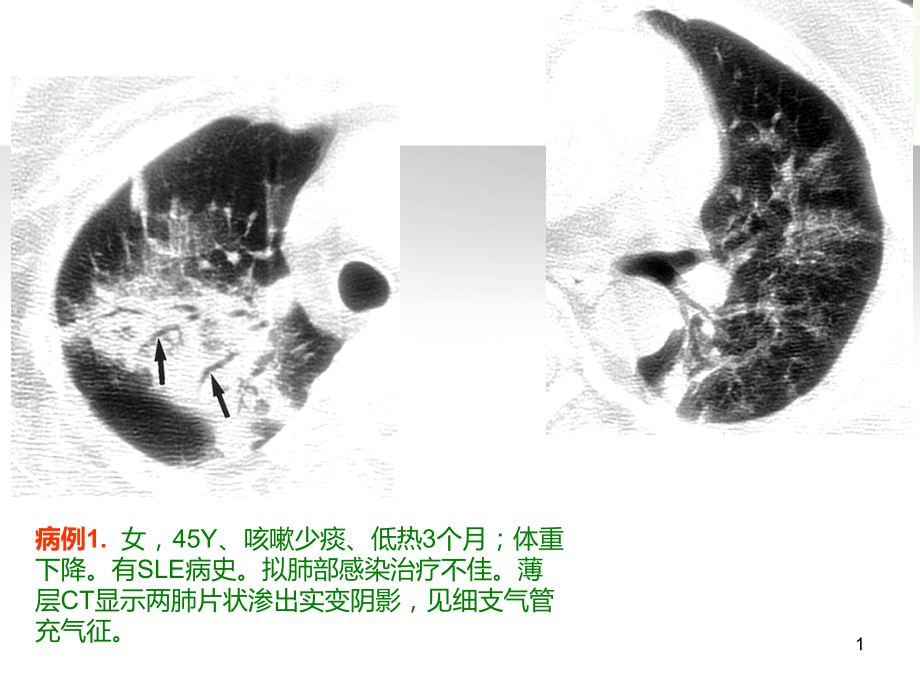

单击此处编辑母版标题样式,单击此处编辑母版文本样式,第二级,第三级,第四级,第五级,*,单击此处编辑母版标题样式,单击此处编辑母版文本样式,第二级,第三级,第四级,第五级,1,病例1.,女,45Y、咳嗽少痰、低热3个月;体重下降。有SLE病史。拟肺部感染治疗不佳。薄层CT显示两肺片状渗出实变阴影,见细支气管充气征。,2,病例2.,F,72Y;咳嗽、白痰、低热并轻度气短半月,白细胞轻度升高,嗜酸性细胞正常;ESR升高;既往无特殊病史。拟诊肺部感染,反复抗炎治疗1月后症状逐渐加重,出现黄痰,一般状态尚好;复查X平片肺部阴影增大。支气管镜显示支气管粘膜炎性改变,少量分泌物,肺泡冲洗液见炎性细胞增多,结核菌(-)真菌培养(+);抗真菌治疗不佳。CT见两肺片状阴影,少量胸腔积液。对比影像,见游走现象,,3,A.大叶性肺炎,B.军团菌肺炎,C.,病毒性肺炎,D.肺结核,E.真菌感染,什么病?,4,下一步?,A.,继续抗感染治疗,B.,实验性抗痨治疗,C.,经皮肺活检,D.,开胸肺活检,临床诊断和治疗过程,穿刺病理,:,肺泡腔机化性肺炎改变;,病理、影像和临床综合分析诊断:,病例1:SLE并发机化性肺炎;,病例2:隐原性机化性肺炎;,经过激素治疗效果良好,病灶明显吸收;,病例2在半年后停药复发,再次治疗效果良好。,5,6,隐源性机化性肺炎-,临床和影像学特点,机化性肺炎(OP)、隐源性机化性肺炎(COP):,概念演进、定义和病理特点;,2.,COP的认识和命名的变迁;,3.,发病机制和病因学研究;,4.,临床特征;,5.,影像学特征:典型和不典型表现;,6.,COP的诊断:CRP诊断模式;,7.,鉴别诊断;,7,机化性肺炎(OP),-,病理学范畴,机化性肺炎(OP),是一类以结节炎肉芽组织过度增殖并填塞肺泡腔、肺泡管和呼吸性细支气管及终末细支气管腔为病理特征的一类疾病。,机化性肺炎是一种与多种病因相关的病理组织学类型。,机化性肺炎(OP)属于病理学概念;,原发OP和继发OP在病理学并无明显差异,病理不能区分二者,;,8,隐源性机化性肺炎,(COP),-,从病理学概念到,CRP范畴,2002年IIP国际共识:,COP属于特发性间质性肺炎IIP的1个亚型;,其相应的临床-放射病理学(CRP)定义:,没有明确的致病原(如感染)或其他临床伴随疾病(如结缔组织疾病)情况下出现的机化性肺炎,。,COP从病理学名称成为一个CRP综合的临床诊断名称;,病理学诊断不再使用COP名称。,9,隐源性机化性肺炎-,病理学特点,COP镜下特点:,呈小叶中心分布的斑片性病灶;其间可夹杂正常的肺泡组织;,以Masson 小体形成为特征:,终末细支气管以下小气道和肺泡腔内疏松的胶原样肉芽组织小结填塞。伴或不伴小气道和肺泡腔狭窄或闭塞;,肉芽组织病变呈均一时相,可通过肺泡孔播散到临近肺泡;,背景的细支气管、肺泡管和肺泡结构相对完整。,肺间质轻度炎症浸润;,10,COP的组织病理学特点,镜下肺泡内胶原样疏松结缔组织肉芽小结,(,Masson 小体,),,沿肺泡孔扩散,箭头。间质炎性细胞浸润,肺泡结构完整。,11,隐源性机化性肺炎概念-,COP的,历史和认识的变迁,1901(Lange):病理学闭塞性细支气管炎(BO);,1969(Liebow):病理学慢性间质性肺炎5个亚型之一:闭塞性细支气管炎间质性肺炎,(BIP);,1983(Davison):提出机化性肺炎的病理学概念:Cryptogenic organizing pneumonia(COP),1985(Epler):闭塞性细支气管炎并机化性肺炎(,BOOP,);,2002对IIP分类国际共识:COP是特发性肺纤维化(IIP)的一个亚型,,COP=,i,BOOP,;,强调CRP诊断模式,,从病理学名称进化到临床诊断名称。,12,隐源性机化性肺炎概念-,COP历史和认识的变迁,2002年ATS/ERS的IIP分类的专家共识:,用机化性肺炎型(OP)和隐源性机化性肺炎(COP)分别描述其病理和临床特征。,COP属于,IIP,中的一种类型;,COP 的发病率位列IIP的第3 位。,2013年ATS/ERS的IIP修订版,重点提供了临床行为特征的临床分类和处理策略:,IIP分为,主要的IIP,、,罕见的IIP,和,不能分类IIP,共3大类。,COP,属于主要的IIP的1个亚型,临床特征为急性/亚急性的伴有进展因素的可逆性病变。,13,弥漫性肺病,(,DPLD,),药物,/CTD/,感染相关,DPLD,特发性间质性肺炎,(IIP),肉芽肿性,DPLD,(结节病),/,其他(,LAM,,,HX,),特发性间质纤维化,IPF,除IPF以外的其他类型的IIP,NSIP,RBILD,LIP,AIP,DIP,COP,2002版 ATS/ERS的IIP分类国际共识,14,特发性间质性肺病,(IIP),主要的,IIP,罕见的IIP,不能分类的IIP,2-20%有家族性,80%无家族性,特发性淋巴细胞IP,LIP,特发性胸膜肺弹力纤维增生,PPFE,吸烟相关IP,脱屑性IP(DIP),呼吸性细支气管炎合并IP,(RBILD),急性纤维素性OP,慢性致纤维化IP,IPF、iNSIP,气道中心性IP,急性/亚急性IP,COP、AIP,2013年 ATS/ERS的IIP分类修订版,15,隐源性机化性肺炎-,临床和影像学特点,COP的概念变迁:定义、病因、病理特点,发病机制和病因学研究;,临床特征;,影像学特征:典型和不典型表现;,COP的诊断:CRP诊断模式;,鉴别诊断;,16,隐源性机化性肺炎概念-,发病机制和病因,COP的发病机制和病因目前尚不十分清楚;,由于起病时多数病人有类似流感样表现,推测可能与感染有关。Elizabeth 等用呼吸道肠病毒复制出BOOP的肺部病理模型,提示呼吸道病毒感染参与COP的形成。,COP的病理机制:,致病因素-终末呼吸道肺泡上皮损伤-毛细血管渗出-肺泡内渗出物炎性肉芽肿-疏松结缔组织肉芽(OP),可逆性增生,;,17,COP的病理机制-,示意图,正常肺泡腔,毛细血管渗出液,炎性肉芽肿结节,胶原样组织肉芽肿小结,18,隐源性机化性肺炎-,临床和影像学特点,COP的概念变迁:定义、病因、病理特点,发病机制和病因学研究;,临床特征;,影像学特征:典型和不典型表现;,COP的诊断:CRP诊断模式;,鉴别诊断;,19,临床表现特点,临床表现无特异性;,发病率男女基本相等;无性别差异,,与吸烟无关,。,发病年龄从18-85岁不等。高峰在50-60岁之间;,多数亚急性起病,个别急性起病。多数病程2-10周;,70%有低热、90%以上咳嗽、少量白痰65%;伴气促40%;15%有乏力、纳差和体重下降;,30%有咯血、18%胸痛,少见关节痛和夜间盗汗。,40-60%有散在的湿性罗音 或Velcro 音;20%以下有胸腔积液;,25-50%病人无明显体征;,有60-90%误诊为肺部感染;,发病后至确诊,90%以上用1-4种抗菌素治疗1-2个疗程以上,平均抗菌素治疗为25天;,20,实验室检查,外周血白细胞总数正常或轻度升高;,中性粒细胞可轻度增高;,血沉和C-反应蛋白明显增高,;,痰找细菌、真菌、抗酸杆菌均为阴性。,抗核抗体、中性性粒细胞胞浆抗体(ANCA)、风湿系列等免疫学检查提示不存在系统性疾病。,肺泡灌洗液的细胞分类中,淋巴细胞(41-59%)和中性粒细胞(5-12%)增高,嗜酸性细胞也可增高,CD4与CD8比值明显降低;,肺功能轻至中度,限制性通气功能障碍,,CO弥散率降低;,21,隐源性机化性肺炎-,概念和诊断模式的变迁,COP的概念变迁:定义、病因、病理特点,发病机制和病因学研究;,临床特征;,影像学特征:典型和不典型表现;,COP的诊断:CRP诊断模式;,鉴别诊断;,22,影像学特点-,典型表现,CT显示两肺多发性小片状肺泡渗出实变影(70%),磨玻璃影(54%)和条索影(25%);多为2种以上影像混合存在。,多在胸膜下区分布(55%)或沿支气管束分布(35%);,病灶边缘模糊,有35-60%病灶内见细支气管充气征;,30-50%病例的病灶显示游走性特点;,10-25%,见少量胸水;,23,COP典型影像-两肺多发小片渗出实变和GGO;胸膜下分布特点。,24,COP影像特点-,典型表现,25,COP影像特点-,典型表现,两肺多发GGO;,沿胸膜下和支气管束分布;,肺纹理增粗、模糊。,26,COP影像特点-,典型表现,两肺多发渗出实变和GGO、条状影;,沿胸膜下和支气管束分布;,27,影像学特点-,不典型表现,单发结节影或团块,病灶,;HRCT可见小空洞;,多发小结节影;,不规则条索影和线状影;,弥漫性大片GGO,反晕征;,28,少见影像表现-,单发团块影,单发团块影;边缘模糊,形态不规整。,29,少见影像表现-,多形性结节和空洞影,30,少见影像表现-,不规则线状影,不规整网状、多边形线样影,条带状线样影,31,COP影像特点-,不典型表现,多发的弥漫的大片状GGO,32,COP影像学特点-,5多1少,特性,1、,多态性:多种影像形态,如实变影、磨玻璃影、,条索影、团块影、结节影、网格影;,2、,多发性:每侧肺可见多个病灶,3、,多两侧受累:多数为两肺累及,4、,多变性:游走迁徙性,病灶此起彼伏,5、,多复发性:激素治疗病灶吸收后容易复发,;,少蜂窝肺:少见胸膜下纤维化蜂窝征象。,33,隐源性机化性肺炎-,概念和诊断模式的变迁,COP的概念变迁:定义、病因、病理特点,发病机制和病因学研究;,临床特征;,影像学特征:典型和不典型表现;,COP的诊断和治疗:CRP诊断模式;,鉴别诊断;,34,COP诊断的变迁-,从病理诊断到CRP临床综合诊断,2002年IIP分类专家共识,与其他IIP一样,COP不是单纯的病理诊断名称,而是结合了,临床-影像-病理诊断,之后的临床诊断名称。,COP诊断须遵循,“,临床-影像-病理诊断,(CRP)”的原则。,COP完成了从过去的病理诊断名称到CRP综合临床诊断名称的蜕变,从而使其成为有独特临床-影像-病理特征的独立病种。,35,COP诊断-,下列临床特点时高度提示COP,以流感样症状亚急性起病,有低热、咳嗽少痰、体重减轻。,肺部有爆裂音。,肺部,多段多叶,的胸膜下,斑片状,阴影,,可,有,游走性;,多种抗生素治疗时病情呈进行性加重;,除外肺结核、支原体和真菌等肺部感染以及胶原病。,患者无大量使用激素、免疫抑制剂的病史或免疫功能受损,病程迁延23 个月,病灶不吸收的原因不好解释。,患者一般状况好而肺部影像表现相对重;,临床表现和影像表现不相称。,36,TBLB/经皮肺活检对COP诊断价值,特发性间质性肺病的确诊需要开胸或经胸腔镜肺活检。,TBLB在特发性间质性肺病的应用主要是除外结节病、肿瘤和某些特殊类型的感染。,2002年ATS/ERS共识中,可通过TBLB/经皮肺穿刺而不需要开胸就能诊断的2类IIP:急性间质性肺炎(AIP)和COP。,对疑诊患者尽早进行TBLB,并结合COP 的“临床-病理-影像”特点做到早期诊断,对改善病人的预后尤为重要。,37,COP的治疗原则及预后,糖皮质激素是目前治疗COP的主要药物,文献报道糖皮质激素起始剂量0.75mg/kg/day,2-4周后减量。总疗程在6-12月。,激素减量或停药过快容易复发。复发率60-80%。,COP 的预后良好;,复发对再次激素治疗有效,且对预后无明显影响。,积极治疗完全恢复60%,不完全恢复30%,死亡率,5%。,死亡病例多为治疗效果不佳的晚期诊断病例。,38,糖皮质激素治疗前后病灶变化,治疗前 治疗后,39,糖皮质激素治疗前后病灶变化,40,隐源性机化性肺炎-,概念和诊断模式的变迁,COP的概念变迁:定义、病因、病理特点,发病机制和病因学研究;,临床特征;,影像学特征:典型和不典型表现;,COP的诊断和治疗:CRP诊断模式;,鉴别诊断;,41,COP鉴别诊断,肺部感染:,包括细菌、真菌、病毒和支原体感染;,除外药物因素引起的继发性机化性肺炎,常见药物有安碘酮,博来霉素,金制剂等;,除外其它血管炎病变,如Wegener肉芽肿、结缔组织病;,需要和其它间质性肺炎鉴别:NSIP中也可见到机化性肺炎样改变,两者影像有一定的相似性,有时鉴别困难。,鉴别诊断应坚持,C-R-P综合分析原则;,及时的,TBLB/经皮肺穿刺,活检非常必要。,42,COP和NSIP影像鉴别,不同层面肺部 CT,可见弥漫性磨玻璃影,小叶间隔增厚,,两者鉴别困难。,COP,NSIP,43,天境祁连,